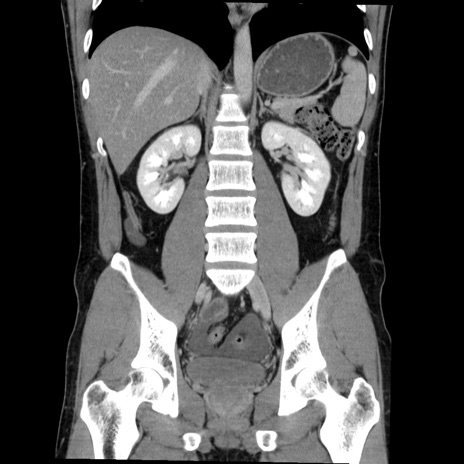

症例36(冠状断像)

【症例】20歳代 男性

【主訴】心窩部痛

【現病歴】今朝より上腹部痛あり。一旦軽快していたが再度出現したため救急要請。昨日夕に白身の魚を含む刺身を食べた。

【身体所見】BP 136/89mmHg、HR 74/min、BT 37.0℃、腹部:膨満、軟、心窩部に圧痛あり。反跳痛なし、筋性防御なし、腸雑音やや亢進あり。

【データ】WBC 17700、CRP 0.48